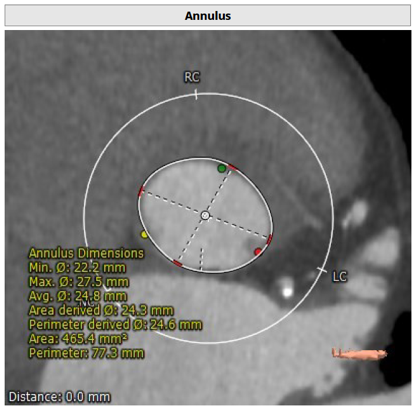

77 岁的男性患者徐某因“劳力性呼吸困难1年余,晕厥2月”就诊于我院心内科并住院接受治疗,入院超声心动图检查发现:主动脉瓣钙化,重度狭窄, 轻度关闭不全,LVEF 50%。诊断为症状性重度主动脉瓣狭窄明确,判断患者符合TAVR 手术指征,无明确手术禁忌症。完善术前CT检查提示(如下图):

佘飞医师及薛亚军医师反复阅读超声及CT评估结果,与张萍教授、王伟民教授、吴永健教授讨论病情后,综合评估结果,决定行TAVR 手术,采用22mm球囊预扩张主动脉瓣,植入26mm Venus-A 瓣膜。通过充分的术前评估与准备,与患者家属反复沟通、告知病情以及相关风险,最终获得家属的手术同意。